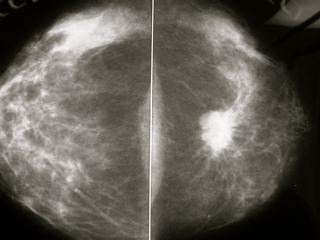

cribado del cáncer de mama